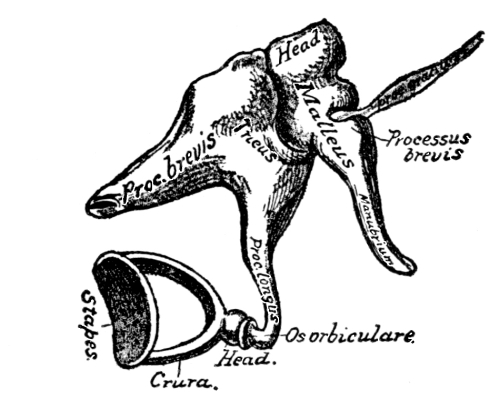

| The Organs of Special Sense | 57 |

The Nose, 57—The Sense of Smell, 58—The Mouth, 59—The Hyoid Bone, 60—The Teeth, 60—The Sense of Taste, 61—Salivary Glands, 61—The Tonsils, 62—The Ear, 63—Eustachian Tubes, 63—Sensation of Hearing, 65—The Eye, 66—Lachrymal Gland, 68—Coats of the Eye, 68—Light Rays and Sight, 70—Accommodation, 72—Color Perception, 73. |